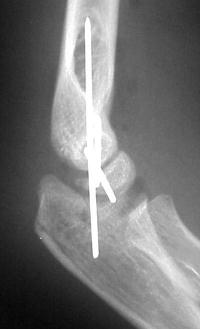

Open reduction and fixation: